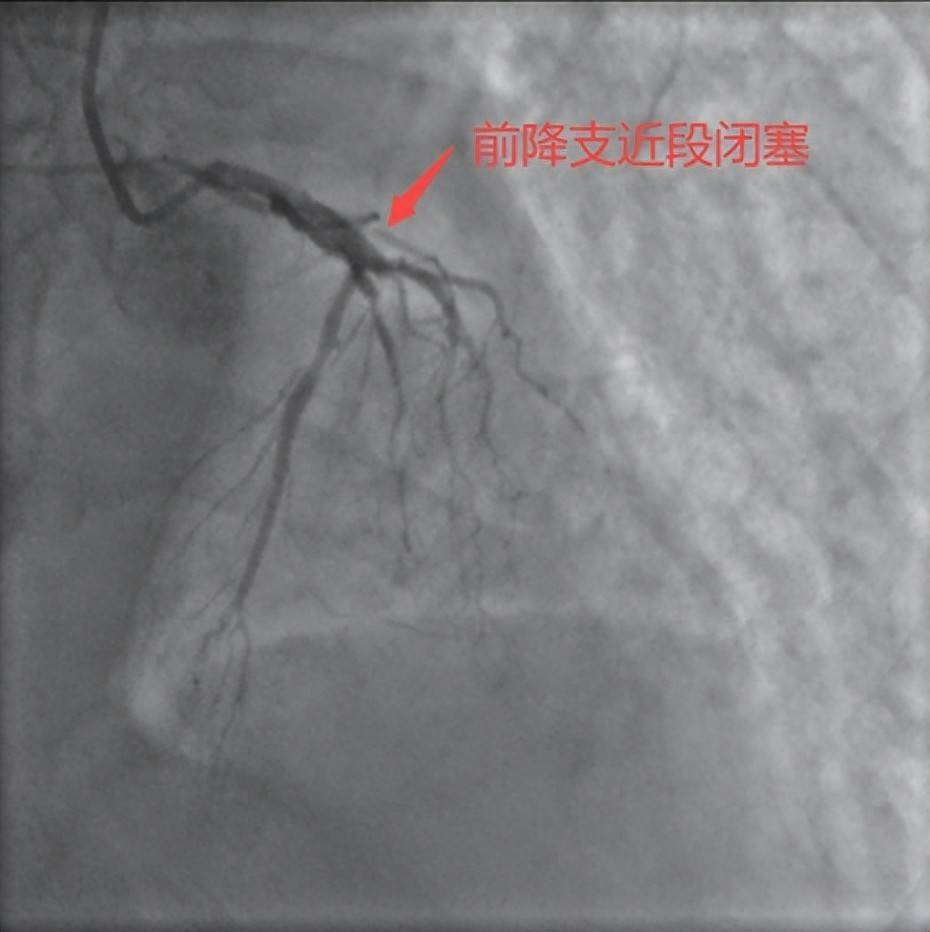

术中冠状动脉造影显示,恶魔丘比特副作用王先生心脏左前降支(LAD)近段完全闭塞,而且由于患者左回旋支细小,整个左心室90%的血液断供,病情极为凶险,稍有延后极可能猝死,治疗的关键在于快速开通血管。心血管内科主任蒋桔泉团队争分夺秒,从进导管室到开通血管、植入支架仅用了20多分钟。术后患者转入重症监护室(ICU),12小时后患者成功呼吸机脱机,48小时后病情稳定,转入心内科普通病房继续治疗1周后康复出院。